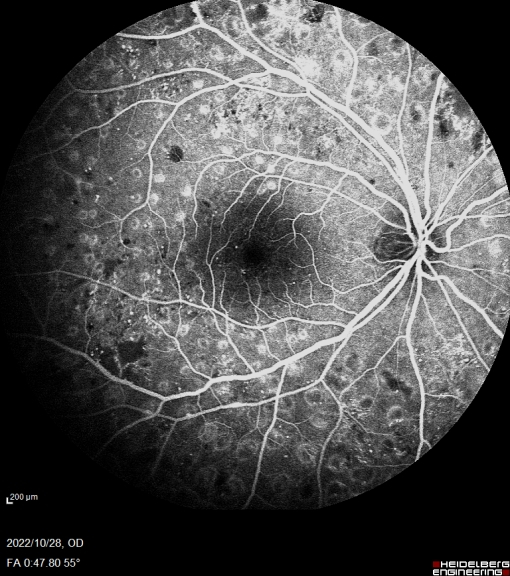

此次合肥普瑞眼科医院引入的海德堡 Spectralis HRA共焦激光同步血管造影系统可配备有“天幕”102°超广角镜头,是造影设备的全新升级。102°超广角造影图像的观察范围更广,有效涵盖周边眼底,可以更早的发现早期糖尿病视网膜及一些血管性疾病的周边部改变,对于控制患者病情发展,减少视力损害意义重大。同时Spectralis HRA还具有动态造影的独特功能,每秒钟可以获取16帧高清图像,全程记录血管充盈过程,不遗漏重要细节。

55°成像

10月28日,眼底病专科副主任张思伟利用海德堡 Spectralis HRA共焦激光同步血管造影系统顺利完成首例患者广角眼底血管荧光造影检查,为眼底病患者后续相关治疗提供有力支持,标志着合肥普瑞眼科医院眼底病专科诊疗水平再上新台阶。未来,合肥普瑞眼科医院将始终秉承“用爱传递光明”的理念,坚持以患者为中心,优化医院重点特色专科建设,全面提升医院各项诊疗服务水平,为人民群众的眼健康保驾护航!